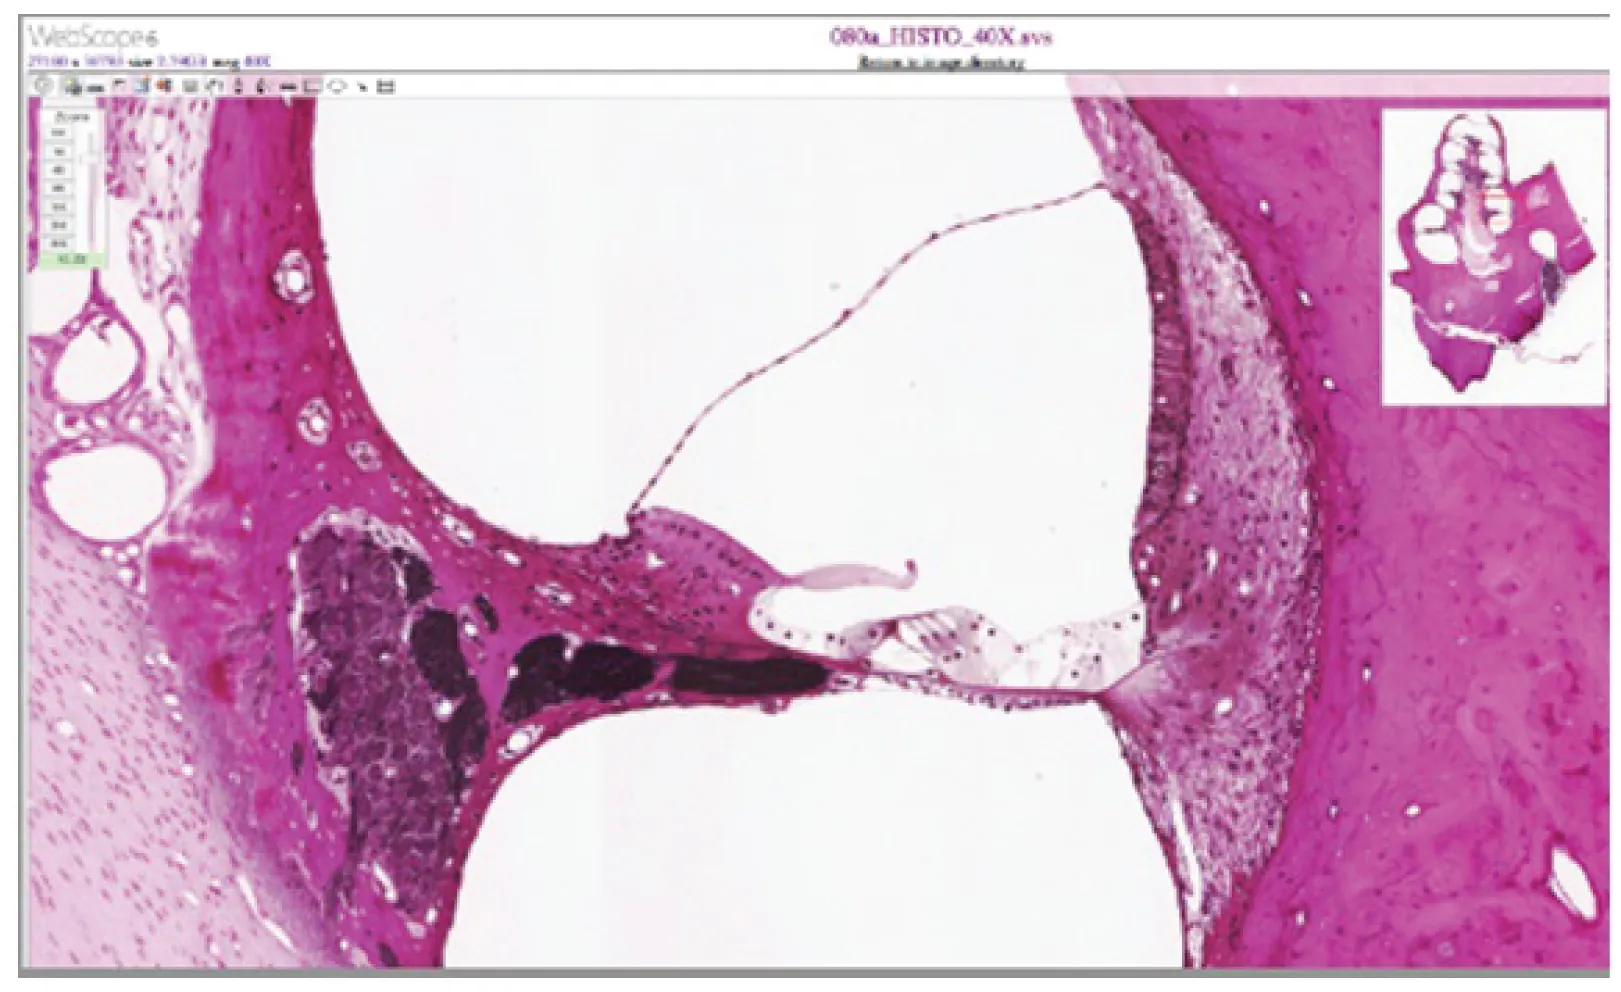

This micrograph shows the ultrastructure of the cochlea.

Figure 14.9 Cochlea and Organ of Corti LM × 412. (Micrograph provided by the Regents of University of Michigan Medical School © 2012)

View the University of Michigan WebScope to explore the tissue sample in greater detail. The basilar membrane is the thin membrane that extends from the central core of the cochlea to the edge. What is anchored to this membrane so that they can be activated by movement of the fluids within the cochlea?